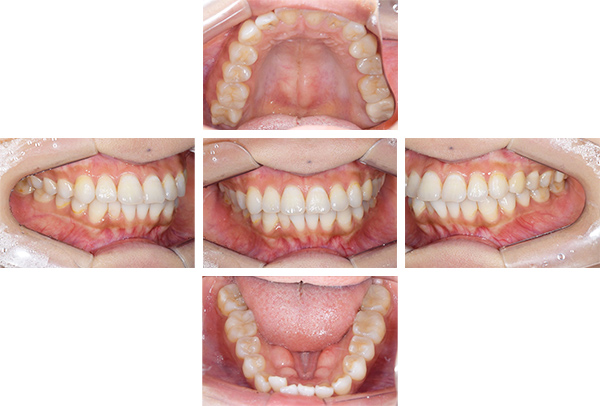

インレー・クラウン・ホワイトニング症例

治療前

治療後

治療期間 11回(4ヶ月)

費用 ・ハイブリッドインレー7本

・ジルコニアクラウン2本

・ホワイトニング:5回

合計:430,500円

治療リスク・副作用 ・詰め物、被せ物をする時は自分の歯を削ることになります

・歯ぎしり・食いしばりが強い方は、セラミックが割れてしまうことがあります。